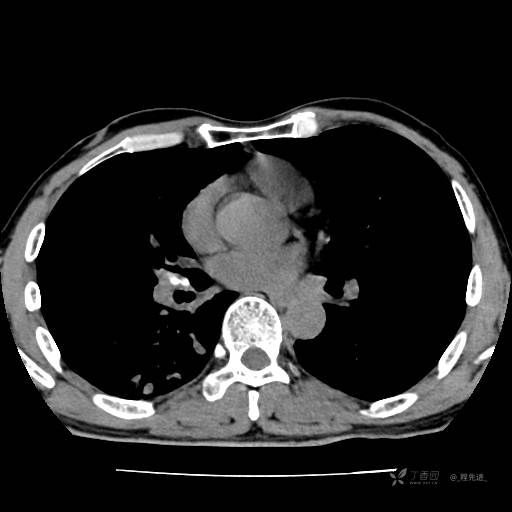

2月特别精彩病例|咳嗽、咳痰20余天,典型病例分享【结果已公布】

患者年龄:51岁

主诉:咳嗽、咳痰20余天

简要病史:20余天前开始出现咳嗽、咳痰症状,阵发性刺激性咳,白色粘痰,不易咳出,无发热,无咯血,无恶心、呕吐等不适,未诊治,咳嗽、咳痰症状持续存在。

体格检查:T:36.3 ℃ P:79 次/分 R:20 次/分 BP:128/64 mmHg,神志清楚,呼吸平稳,双肺呼吸音粗,右下肺闻及细湿性啰音。心率79次/分,节律整齐,各瓣膜听诊区未闻及病理性杂音。腹部未见异常,双下肢无水肿。

辅助检查:我院门诊胸部CT示:如下。心电图:窦性心律;正常心电图。